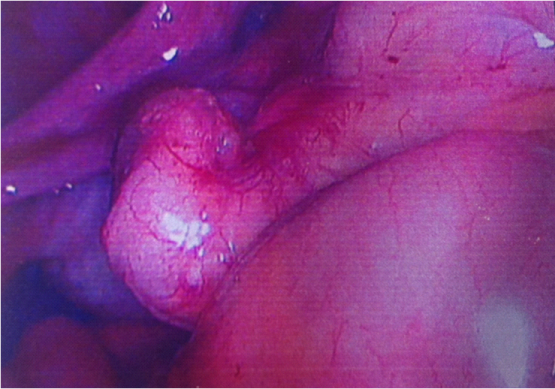

Figure 1: Right lateral bowel adhesions were dissected and endometriomas were excised from both ovaries and were mobilised as per RCOG guidelines.2 The dye test revealed the left tube was patent and the right blocked. Overall, grade 4 endometriosis was noted. On further visualisation of the abdomen, a suspicious looking mucoid lesion on the tip of the appendix was seen and biopsied.

Figure 3: The patient underwent a right hemicolectomy during which further endometriotic deposits were seen. The appendix appeared abnormal as it was thickened and adherent to caecum with mucinous material extruding from the tip. Three proximal puckered lesions were noted in last 20cm of the terminal ileum but no other peritoneal disease was noted.